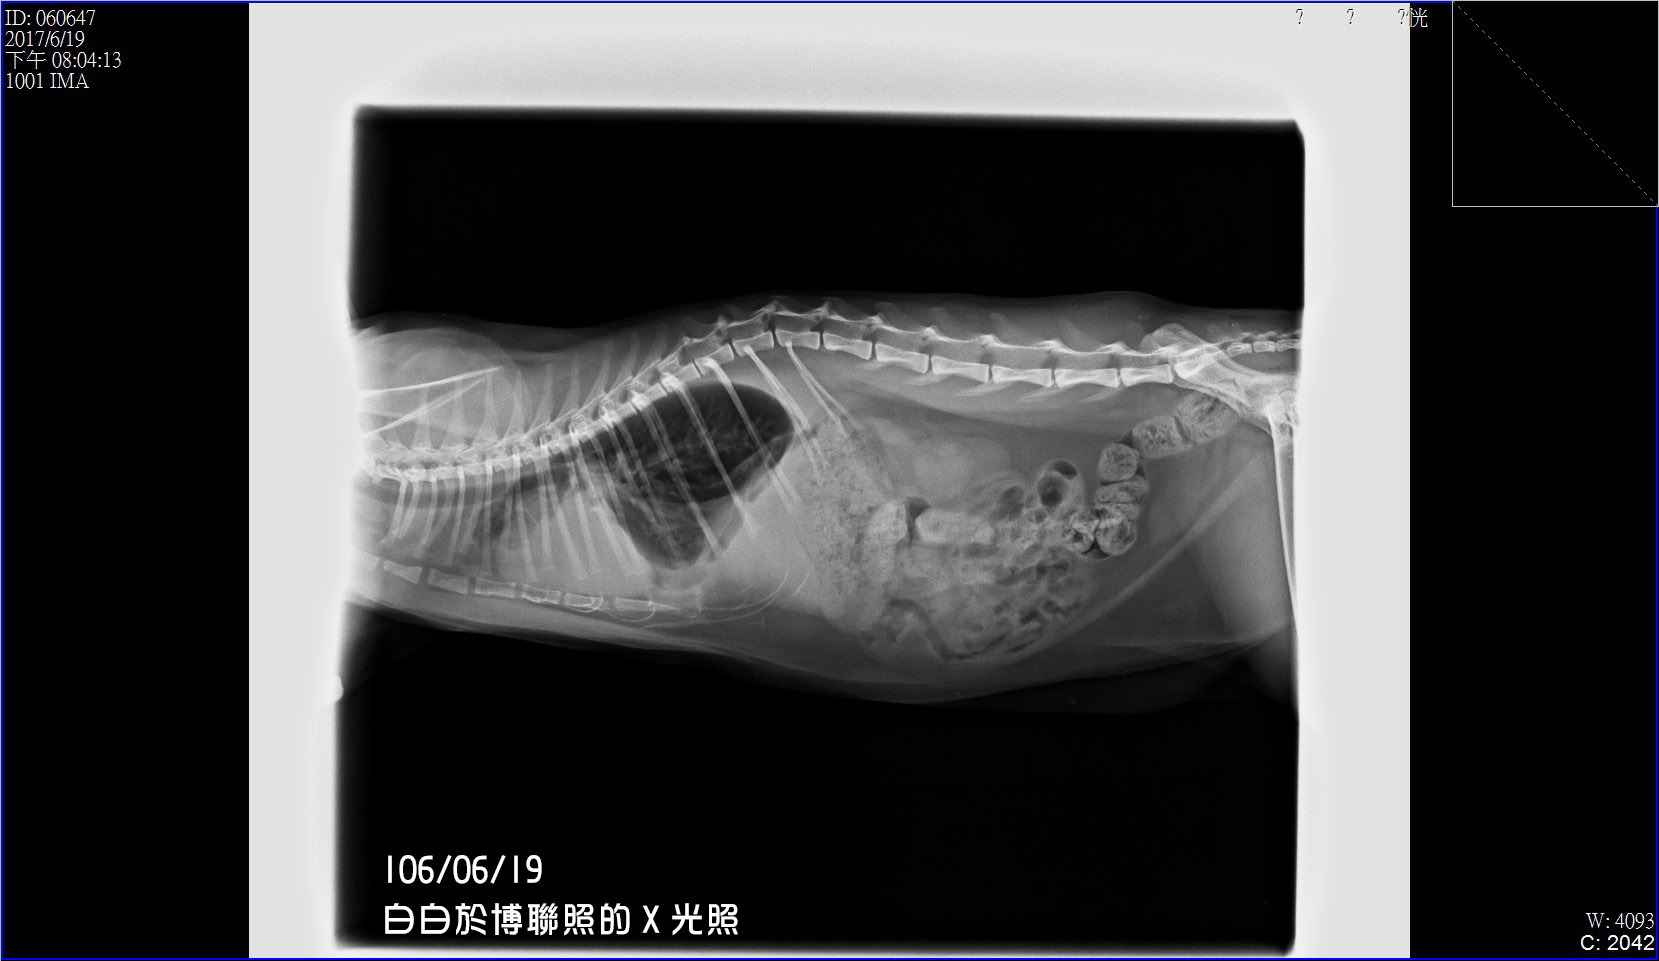

6/19下班後,我準備了所有資料與白白到了博聯,

醫生先照了X光片後,就發現白白的心臟比一般貓大,

於是開始進行照心臟的超音波ㄧ系列的檢查。

在這項檢查裡檢查出白白有「心房隔離缺損」,

二尖瓣閉鎖不全、三尖瓣閉鎖不全,導致心臟擴大。

目前的水還不多,但等到下次回診時,

還是要把目前內部的胸水全抽走。

但現階段導致白白的膿胸症狀,

還不能確定是否因為心臟的疾病導致乳麋胸,

仍先要排除是否心臟病而引起的,

如果心臟病受到控制,

也許這樣的跡象就會慢慢消失也不定。